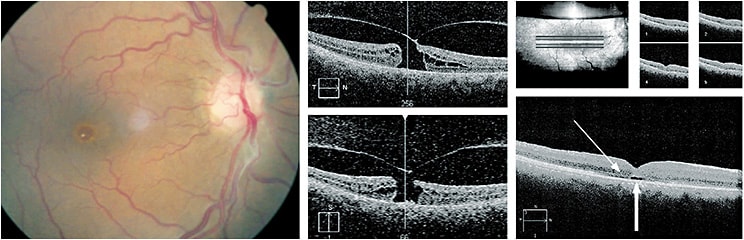

Other applications of OCT include the imaging of pigmented and elevated lesions of the ocular fundus. An example: a 57-year-old female was referred for imaging of an elevated retinal lesion, which had been observed without change over several years. Baseline clinical characteristics did not qualify it as high risk.9,10 The OCT allowed for baseline quantification of lesion height. In addition, an incidental, but clinically invisible, retinal pigment-epithelial detachment was seen (Figure 6).